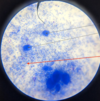

Trypanosoma sp.: Trypomastigotes

Blood smear